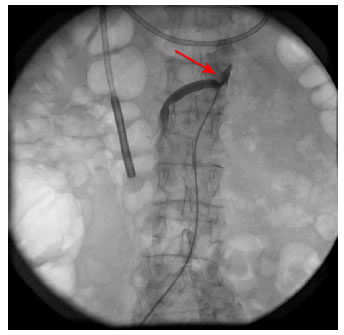

Por el riesgo de trombosis mesentérica e isquemia intestinal grave, la paciente se sometió a una angioplastia periférica de la arteria mesentérica superior con colocación de una endoprótesis (stent), procedimiento se que llevó a cabo sin complicaciones (figura 3).

Figura 3.

Aortograma. La flecha roja muestra la endoprótesis (stent)

en la arteria mesentérica superior.